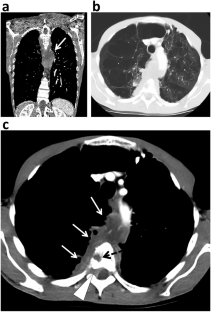

Of the 21 included patients (median age 48, range 30–74), 18 (85.7%) were male and 18 (85.7%) had a smoking history. Four main radiological patterns were identified depending on the location of the main tumor burden: mediastinal (n = 13), pleural (n = 6), cervical (n = 1), and retroperitoneal (n = 1). Median size was 120 mm (range 46–266). Characteristic CT imaging features of primary tumors included ill-defined margins (n = 21), heterogeneous enhancement after injection (n = 20), multi-compartment extension from mediastinum to lung apex, pleura, or neck (n = 20), compressive effect responsible for atelectasis (n = 11), vascular encasement (n = 16—5 superior vena cava syndrome), and esophagus invasion (n = 5). Primary tumors showed strong 18F-FDG avidity in eight patients with PET-CT. Necrotic lymphadenopathies were found in 19 patients, with a surrounding infiltrate in 13 patients. Metastatic locations at baseline mainly involved adrenal (n = 10), lung (n = 6), and bone (n = 5). Median overall survival was 5 months (range 1–13).

Most SMARCA4-DTS present with compressive and infiltrative chest masses with ill-defined necrotic lymphadenopathies. The diagnosis of SMARCA4-DTS should enter in the differentials of the radiologist, especially in the case of a rapidly evolving thoracic mass in young smoking males.

• SMARCA4-DTS, which is mostly located in the chest cavity, can compress and infiltrate all adjacent organs leading to superior vena syndrome, lung atelectasis, epiduritis, spinal cord compression, and esophagus invasion.

• SMARCA4-DTS typically demonstrates several ill-defined necrotic lymphadenopathies spreading in axillar, subclavian, cervical, mediastinum, and retroperitoneum.